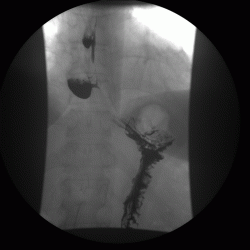

А это тоже дивертикул????

Изображение

Это тоже дивертикул???

или это два дивертикула, которые наложились друг - на друга?

Да это один и тот же больной.Гистологическая верификация-аденокарцинома.И в кишке и в пищеводе дивертикулы.

Случай интересный, в плане сочетания дивертикула пищевода и тонкого кишечника с органикой желудка.